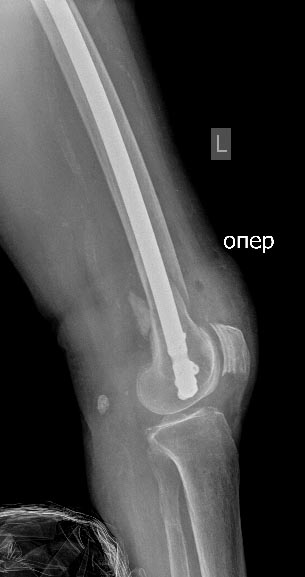

Огромное спасибо коллеги, пациентку 15/01/14 прооперировали, одномоментно (1 бригада), синтезировали блокирующими пластинами

Контрольные рентгенограммы